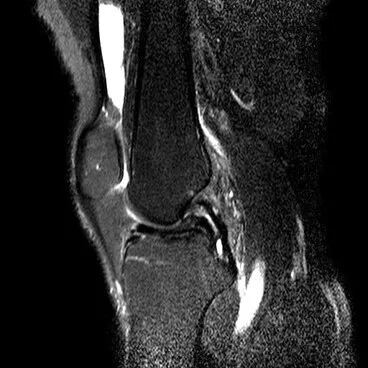

半月板水平撕裂

1、水平撕裂

2、较少见3、III级高信号与胫骨平台平行,到达半月板的游离缘或一侧关节面

(半月板水平撕裂)